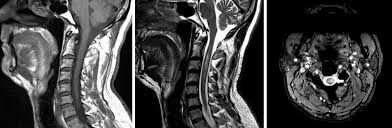

Neuroimaging In Acute Transverse Myelitis Neuroimaging Clinics from els-jbs-prod-cdn.jbs.elsevierhealth.com G37.3 acute transverse myelitis in demyelinating disease of central nervous system g37.4 subacute necrotizing myelitis of central nervous system g37.5 concentric sclerosis balo of central nervous system g37.8 other specified demyelinating diseases of central nervous system g37.9 demyelinating disease of central nervous system, unspecified Transverse myelitis postsurgical spine avm brachial plexus post radiation therapy, eval for mass lesions, entrapment, denervation cervical spine w and w/o contrast 72156 thoracic disc disease pain radiculopathy trauma thoracic spine w/o contrast 72146 tumor infection ms syrinx transverse myelitis postsurgical spine avm The av shunt is located inside the dura mater close to the spinal nerve root where the arterial blood from a. In the acute setting, there is often associated contrast enhancement. Compression of the upper spinal cord, multiple sclerosis, transverse myelitis, behçet's disease, osteogenesis imperfecta lhermitte phenomenon , also called the barber chair phenomenon , is an uncomfortable electrical sensation that runs through the back and into the limbs. Rare neurological complications include transverse myelitis and/or cauda equina syndrome 20, 21; Jan 14, 2017 · transverse myelitis is an inflammatory condition of the spinal cord associated with rapidly progressive neurologic dysfunction. They most commonly affect elderly men and are classically found in the thoracolumbar region.

Supplemental Materials For Evaluation And Management Of Longitudinally Extensive Transverse Myelitis A Guide For Radiologists Clinical Radiology from els-jbs-prod-cdn.jbs.elsevierhealth.com In the acute setting, there is often associated contrast enhancement. Jan 14, 2017 · transverse myelitis is an inflammatory condition of the spinal cord associated with rapidly progressive neurologic dysfunction. Transverse myelitis postsurgical spine avm brachial plexus post radiation therapy, eval for mass lesions, entrapment, denervation cervical spine w and w/o contrast 72156 thoracic disc disease pain radiculopathy trauma thoracic spine w/o contrast 72146 tumor infection ms syrinx transverse myelitis postsurgical spine avm They most commonly affect elderly men and are classically found in the thoracolumbar region. As part of a health sciences university, baylor medicine in houston, texas puts the latest treatments, innovations, and therapies in the hands of its highly trained doctors and care teams, who are working together to develop and deliver a care plan personalized for you. Rare neurological complications include transverse myelitis and/or cauda equina syndrome 20, 21; Compression of the upper spinal cord, multiple sclerosis, transverse myelitis, behçet's disease, osteogenesis imperfecta lhermitte phenomenon , also called the barber chair phenomenon , is an uncomfortable electrical sensation that runs through the back and into the limbs. G37.3 acute transverse myelitis in demyelinating disease of central nervous system g37.4 subacute necrotizing myelitis of central nervous system g37.5 concentric sclerosis balo of central nervous system g37.8 other specified demyelinating diseases of central nervous system g37.9 demyelinating disease of central nervous system, unspecified